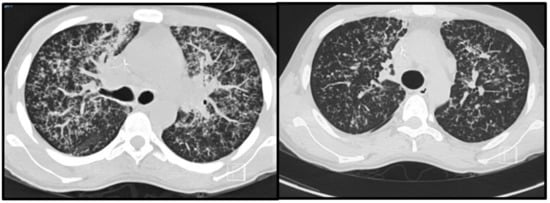

- Rosa Júnior, M.; Baldon, I.V.; Amorim, A.F.C.; Fonseca, A.P.A.; Volpato, R.; Lourenço, R.B.; Baptista, R.M.; de Mello, R.A.F.; Peçanha, P.; Falqueto, A. Imaging Paracoccidioidomycosis: A Pictorial Review from Head to Toe. Eur. J. Radiol. 2018, 103, 147–162. [Google Scholar] [CrossRef]

- Marchiori, E.; Valiante, P.M.; Mano, C.M.; Zanetti, G.; Escuissato, D.L.; Souza, A.S.; Capone, D. Paracoccidioidomycosis: High-Resolution Computed Tomography–Pathologic Correlation. Eur. J. Radiol. 2011, 77, 80–84. [Google Scholar] [CrossRef]

- Muniz, M.; Marchiori, E.; Magnago, M.; Moreira, L. Paracoccidioidomicose Pulmonar: Aspectos Na Tomografia Computadorizada de Alta Resolução. Radiol. Bras. 2002, 35, 147–154. [Google Scholar] [CrossRef]

- Souza, A.S.; Gasparetto, E.L.; Davaus, T.; Escuissato, D.L.; Marchiori, E. High-Resolution CT Findings of 77 Patients with Untreated Pulmonary Paracoccidioidomycosis. Am. J. Roentg. 2006, 187, 1248–1252. [Google Scholar] [CrossRef]

- De Pina, D.R.; Alvarez, M.; Giacomini, G.; Pavan, A.L.M.; Guedes, C.I.A.; de Souza Cavalcante, R.; Mendes, R.P.; Paniago, A.M.M. Paracoccidioidomycosis: Level of Pulmonary Sequelae in High Resolution Computed Tomography Images from Patients of Two Endemic Regions of Brazil. Quant. Imaging Med. Surg. 2017, 7, 318–325. [Google Scholar] [CrossRef]

- Restrepo, A.; Benard, G.; de Castro, C.; Agudelo, C.; Tobón, A. Pulmonary Paracoccidioidomycosis. Semin. Respir. Crit. Care Med. 2008, 29, 182–197. [Google Scholar] [CrossRef]

- Queiroz-Telles, F.; Escuissato, D. Pulmonary Paracoccidioidomycosis. Semin. Respir. Crit. Care Med. 2011, 32, 764–774. [Google Scholar] [CrossRef]